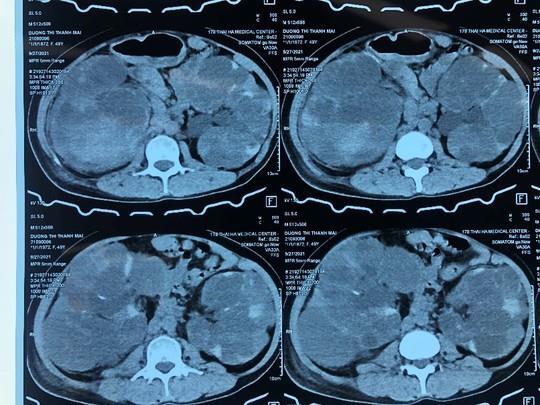

Hình ảnh thận đa nang 2 bên, nang thận phải chảy máu. (Ảnh: Bệnh viện cung cấp)

Theo bác sĩ Trần Đức Dũng, Khoa Tiết niệu, Bệnh viện Trung ương Quân đội 108, thăm khám cho thấy bụng bệnh nhân to, căng chắc cả 2 bên, bên phải to hơn, ấn đau bên phải, thể trạng yếu, hội chứng thiếu máu, hình ảnh CT Scan hệ tiết niệu: thận đa nang 2 bên, bên phải có hình ảnh chảy máu trong nang kích thước thận lớn 15 cm. Soi bàng quang có máu đỏ phun từ thận phải.